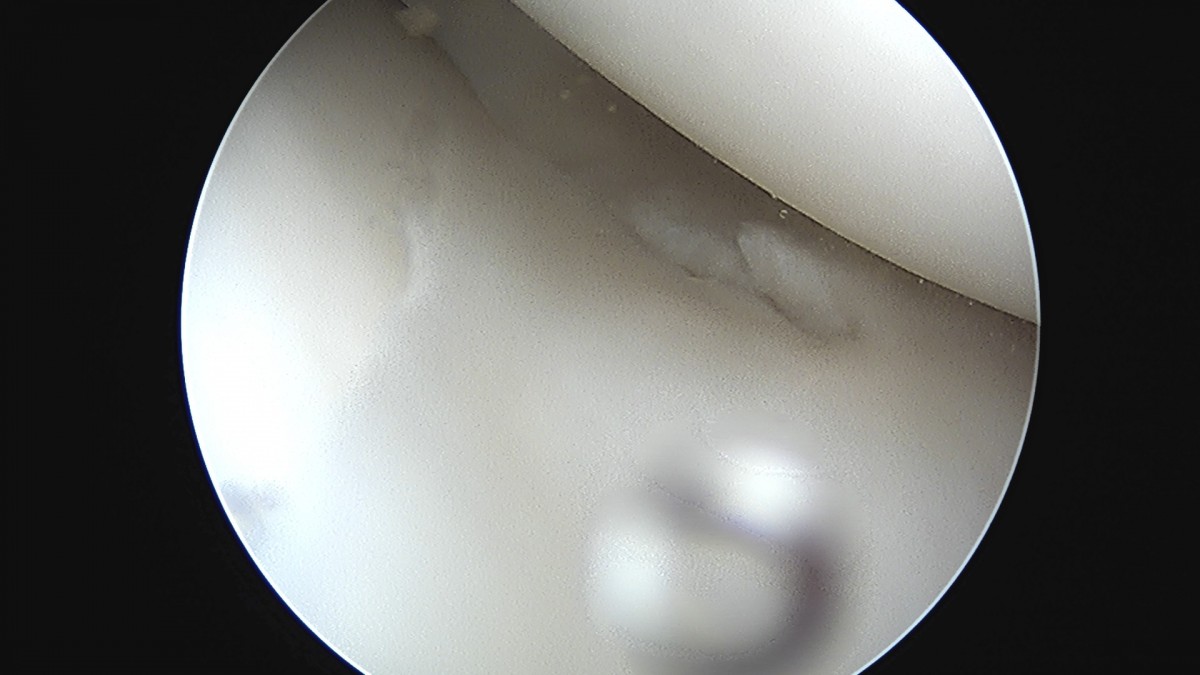

이재상원장님 무릎 반월상 연골판 절제술 김건O 환자

dae765e4d9ac96aee867c9d6292d8784_1758006494_0555.jpg